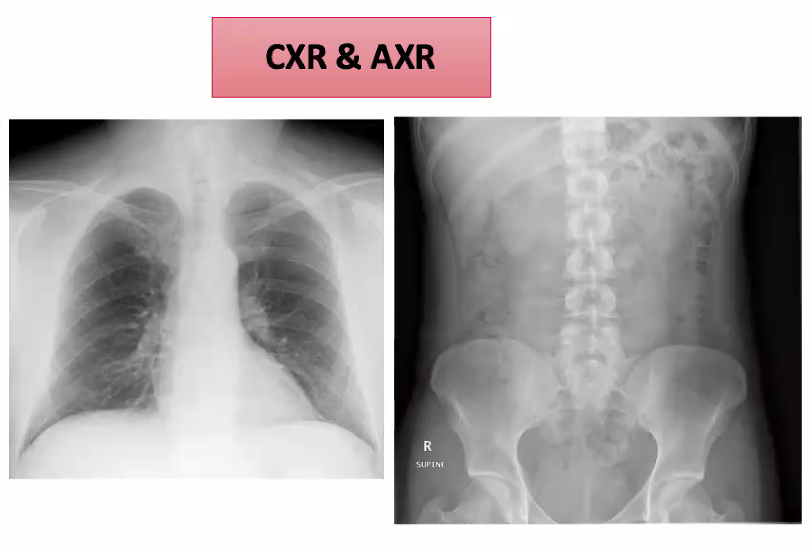

Had bloods, so what is the next investigation? This is the most common if someone comes to a and e presenting with abdominal pain

Do an erect chest X-ray, specifically to check for any chest problems which could cross over to cause abdominal pain, and more specifically look to see if they have any sub diaphragmatic air which may be consistent with a perforation.

Do an abdominal X-ray too

Abdominal and chest x ray are first when coming to a and e, as can point out obvious problems.